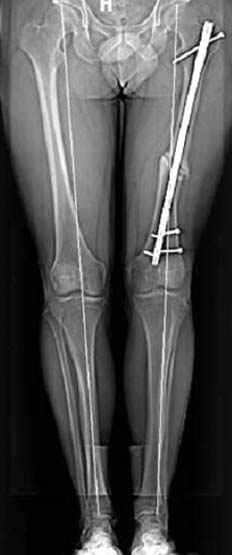

Если, например, доводится лечить больных с псевдартрозами шейки бедра, то надобность есть, и приходится. См. приложение.

Несколько снимков из моей коллекции, чтобы разьяснить, почему мы до сих пор делаем различные варианты остеотомии.

На рисунке N1 предоперационный план лечения ложного сустава шейки бедра- линия ложного сустава, угол и направление введения импланта, клиновидная остеотомия в градусах и миллиметрах, второй снимок после коррекции, расчет, на сколько удлиняется конечность и размеры импланта;

N3 рисунок окончательный снимок, после операции моя рентгенограмма должен выглядеть примерно как эта картина. На N4 снимке клин перед удалением; N5 послеоперации 3 нед.; N6 окончательная рентгенограмма.

(доложен в Ст. Петербурге 2003 и в Москве 2004)

варус при проксимальном отделе 95 градусной пластиной.

Отправитель: Djoldas Kuldjanov 23 Ноябрь 2004, 18:21

пластическая модель; и коррекция бедра аппаратом Илизарова.

Отправитель: Evgueny Tschekashkin 23 Ноябрь 2004, 21:28

Почему не замена гвоздя с рассверливанием, а аппарат?

Отправитель: Alexander Chelnokov 23 Ноябрь 2004, 21:29

Попробую угадать - была инфекция?

Отправитель: Evgueny Tschekashkin 24 Ноябрь 2004, 21:09

хотя даже если бы и инфекция , то nail exchange с рассверливанием канала - вариант дебрайдмента) Я думаю, что последовательность развития событий:

Узкий к-м канал - тонкий гвоздь- усталостный перелом дистальных винтов - развитие нестабильности и как ее результат остеолиз вокруг гвоздя - деформация анатомической оси бедра. Похоже, что я понял почему аппарат, а не новый гвоздь:-)

Отправитель: Alexander Chelnokov 24 Ноябрь 2004, 21:11

ET> хотя даже если бы и инфекция , то nail exchange с рассверливанием канала -

Да, но если, скажем, течет из инфицированных каналов запирающих винтов, да инфекция в дистальном метафизе бедра - устанешь сверлить.

Аппарат в таком случае средство из серии "тише едешь - дальше будешь".

ET> Я думаю, что последовательность развития событий:

[...]

ET> деформация анатомической оси бедра.

Да, наверно. Но если ничего другого нету, ту небольшую деформацию можно было устранить дистрактором одномоментно ввести другой гвоздь.

ET> Похоже, что я понял почему аппарат, а не новый гвоздь:-)

• Re: Hip joint

Отправитель: Evgueny Tschekashkin 24 Ноябрь 2004, 21:13

> Да, но если, скажем, течет из инфицированных каналов запирающих винтов, да инфекция в дистальном метафизе бедра - устанешь сверлить.

ЕТ-Теоретически это возможно, а практически трудно представить - все-таки уровень медицинского сервиса высок, поэтому вряд ли инфекционное воспаление может зайти так далеко.....

> Тогда делись догадкой скорей!

ЕТ - Изначально костно-мозговой канал бедра был узкий, дальнейшее его рассверливание ещё больше скомпрометирует прочность бедра( латеральный кортекс дистального отломка уже истончен), приведет к дефекту наружной стенки - хотя это только мои догадки - хотелось бы знать мнение Джолдаса о выбранной тактике.